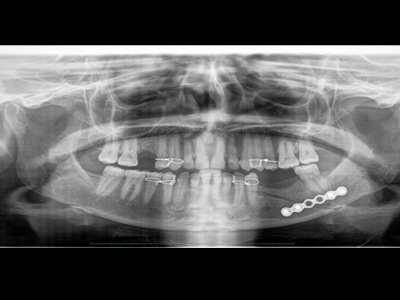

Fractures of jaws and facial bones

road side accidents, falls, sports injuries sometimes lead to fractures of facial bones and jaws .In such cases fractured bone fragments are replaced in their correct position and fixed by various means. Cuts on the skin are repaired by plastic surgical methods to minimize unaesthetic scarring.

Dental implants

Lost teeth can be most appropriately replaced by dental implants. They feel and look very close to our natural teeth. Implant teeth are based on small screws that are placed in our jaws by a small painless surgery mostly under local anaesthesia.